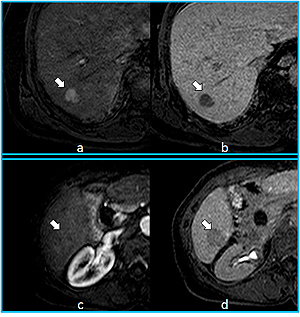

肝臓癌(上段は悪性度が高い癌、下段は悪性度が低い癌)

図の左側は造影剤注入直後、右側は注入15分後の画像です。図の上段は早急に治療が必要な癌で、造影剤注入直後は白く(a 矢印)、15分後には黒く(b 矢印)描出されます。一方、下段の悪性度が低い癌は、注入15分後のみ描出されます(c、d 矢印)。このように悪性度を正確に診断できるため、治療を適切な時期に行うことが可能です。